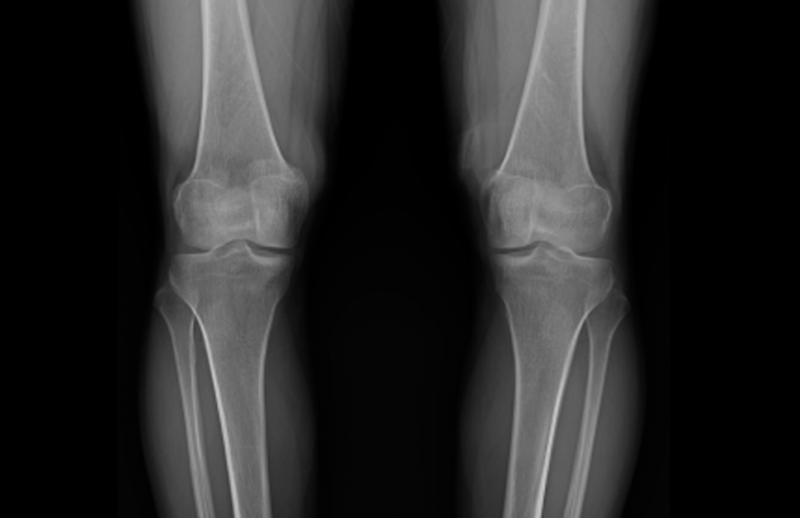

우선적으로 가장 중요한 것은 본인의 휜다리 유형을 살펴보는 것입니다.

O다리, X다리 유형을 살펴보고 관절의 회전이 동반 되었는지, 대퇴골과 경골은 어떻게 회전되었는지 확인합니다.

부산오다리, 엑스다리교정 전문병원을 방문하셔서 검사를 받아보시는 것이 좋습니다.

휜다리 검사와 X-ray를 통해서 확인해볼 수 있습니다.